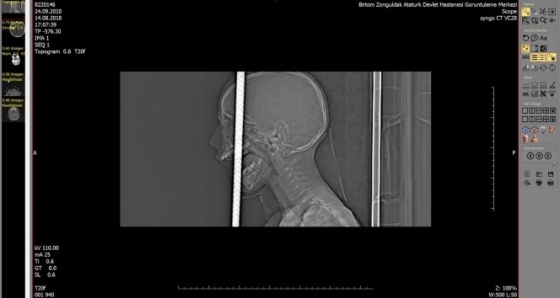

Zonguldak’ta kafasına demir saplanması sebebiyle Bülent Ecevit Üniversitesi Uygulama ve Araştırma Merkezine sevk edilen 7 yaşındaki Fırat Başaran’ın başındaki 1 metre uzunluğundaki demir çubuk, alanında uzman 7 doktor ekip tarafından 6 saat süren operasyonla çıkartıldı.

Zonguldak'ta, bisikletiyle gezerken 2 metre yükseklikten düşen 7 yaşındaki Fırat Başaran'ın ağzından giren demir başından çıktı.

Temel prensip ilk önce zarar vermeme, üst damaktan ağız içinden giren ve yaklaşık 1 metre uzunluğundaki demir çubuk kafatasını delerek sol ön fontelden 40 santim dışarı çıkmıştı.

AFAD ekipleri tarafından 3 santim kalana kadar kesildi. Temel prensiplere bağlı kalarak parçalanan bölgeyi genişleterek demir çubuk rahatlatıldı.

Sonra ameliyata alınarak demir çubuk çıkartıldı. Ön beyin düşünce davranışlarımızı yönlendirir; hafıza, düşünme, karar verme, idare etme gibi durumları evet çocuğumuz şu an yoğun bakımda bilinci açık bir şekilde zaman içinde neyi kaybettiğini görmüş olacağız.